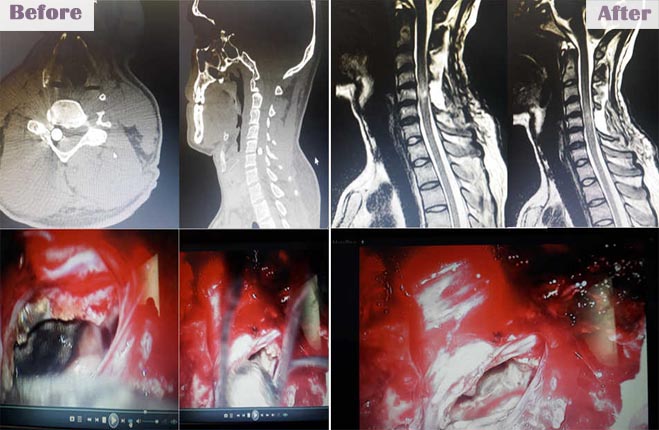

- Spine surgery - More than 3000 spinal surgeries including 40 spinal tumors microdiscectomy, MIS TLIF, artificial disc replacements, multilevel corpectomy, CV junction stabilization.

- Brain tumors - More than 1800 including pituitary, posterior fossa, intraventricular lesions, suprasellar lesions and intrinsic brain tumors